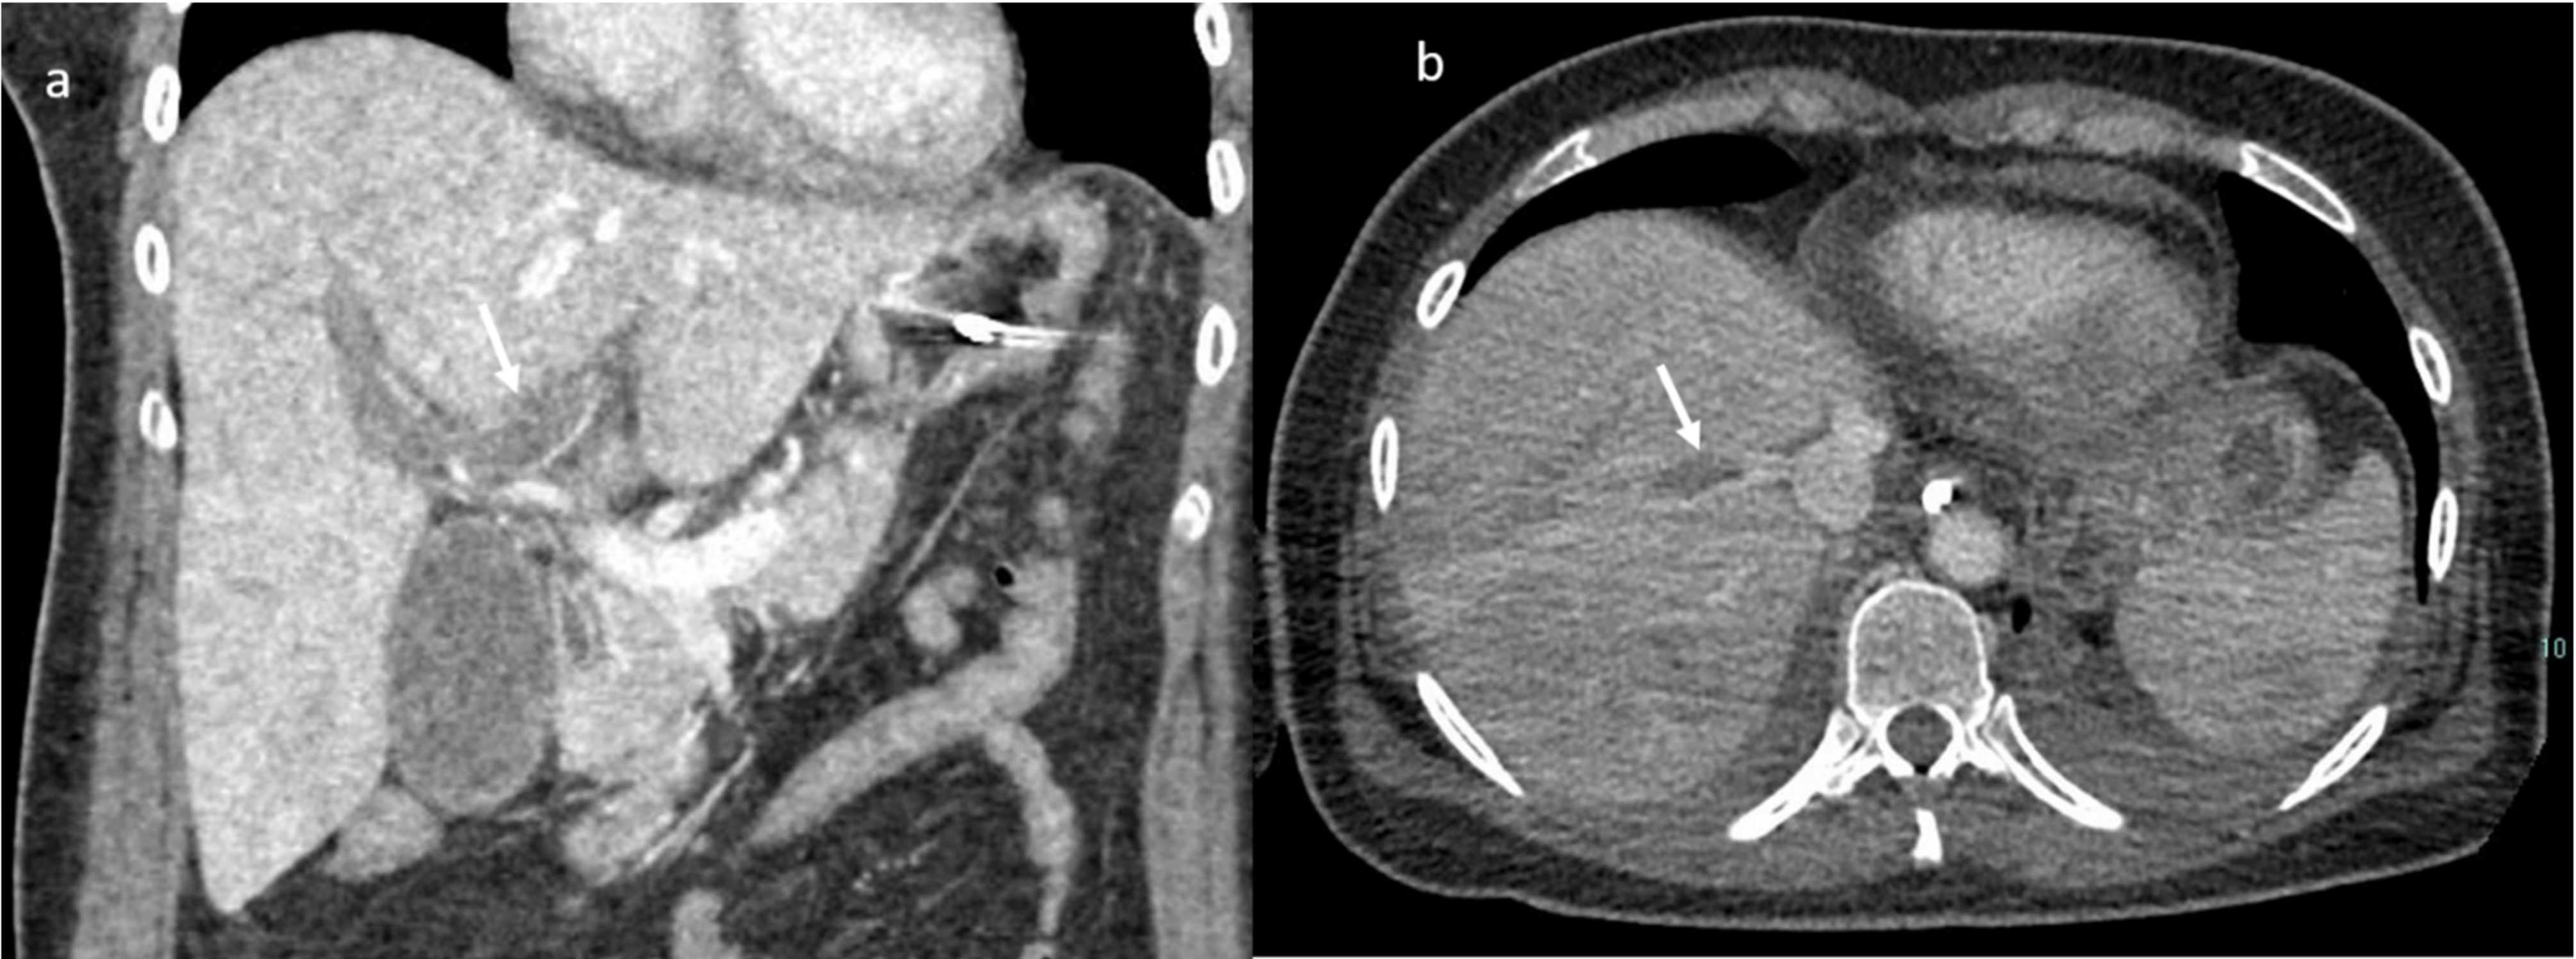

An abdomen angio-CT showed filling defects at the level of left portal branch (Figure 7) and at the level of right suprahepatic vein (7). Bilaterally, it was adrenal hemorrhage (Figure 8) and blood in the pelvis.

Figure 7.

CT scan; in (a) MPR (arrow shows thrombosis of the left portal branch) and in (b) axial plain during portal phase arrow shows thrombosis if the right (Figuer suprahepatic vein).